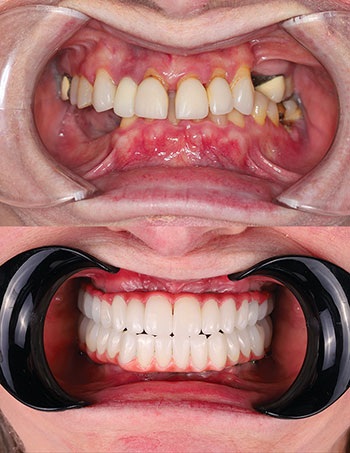

After thorough evaluation, we planned for a FP3 restoration in the maxilla and mandible (implant-supported crowns that mimic natural teeth and allow for flossing) and a fixed prosthesis with pink material to replace tissue contours.

Thanks to close collaboration with LA Dental Implant Lab, we were able to redesign and mill a custom titanium substructure to ensure passivity and a precise fit. We used zirconia thimble supra structure design and individual crowns to allow flossing through embrasures. This fabricated individual, highly aesthetic zirconia crowns, creating a natural-looking, functional and hygienic restoration (Figs. 13–14).

Final seating: Perfect fit, zero adjustments

Final delivery day could not have gone smoother. No adjustments were needed—a testament to precision planning and execution along with digital workflows. Patient satisfaction was beyond expectations—she could floss between her teeth, enjoy a natural smile and eat comfortably. The occlusion was balanced and aesthetics were on point, and the patient left with tears of joy (Figs. 15–17).

Follow-up and long-term outcome: Two years of stability

Today, two years after final delivery, the patient remains stable with no mobility, inflammation or prosthetic complications. There is excellent soft tissue health around the implants. Full function was restored and the patient enjoys all foods without restrictions. Radiographs show stable bone levels around all implants, including the pterygoid site (Fig. 18).